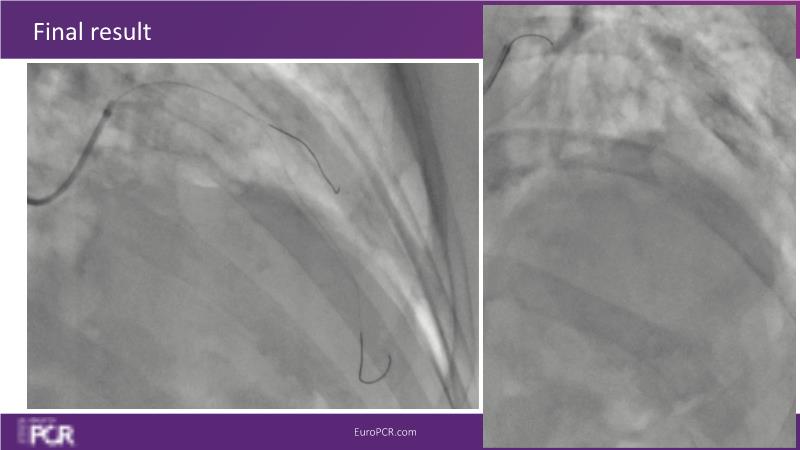

Through the study of two cases, this session examines the need for stenting bifurcation lesions and the role of DEB technology in avoiding stent-related complications in long diffuse disease. It emphasizes the benefits of SELUTION SLR balloons for de novo lesions, discussing how sustained limus release technology can broaden DEB indications and reduce metal usage, understanding the limitations of DES and the emerging role of DEB with sustained limus release, and learning how to identify dissections that can be left unstented.